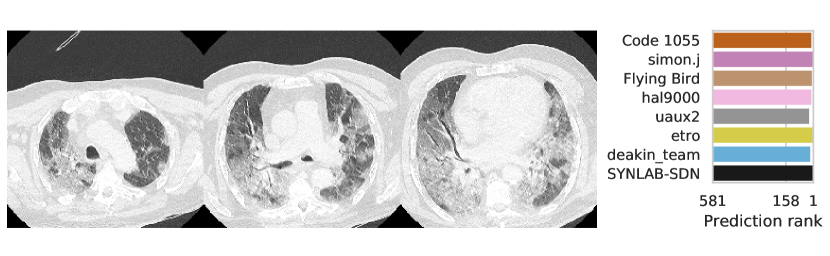

3.2.3 Performance

Table 1 shows the AUC on test set B for COVID-19 presence and severity of the teams that submitted to the Final phase. Figure 4 shows Receiving Operating Characteristics (ROC) curves of the six successful Final phase submissions for discriminating between severe and non-severe COVID-19 subjects from test set B. Figures 5 and 6 show how the finalists ranked the subjects from test set B with severe and non-severe COVID-19 respectively for presence of severe COVID-19. Figures 7 and 8 highlight some individual cases from test set B. During the original STOIC project [67], a logistic regression model was developed to predict severe COVID-19 using clinical variables and CT annotations by radiologists. It was developed and evaluated using the patients from the STOIC who were COVID-19 positive for both RT-PCR and CT, and had unenhanced CT. Of these 4238 patients, 1000 developed severe COVID-19. Revel and colleagues 6 reported an AUC for this model of 0.69 (CI: 0.67-0.71). To compare this model against the results from STOIC2021, an ensemble of the top three solutions for severe COVID-19 prediction was evaluated on the 367 patients from test set B who were COVID-19 positive for both RT-PCR and CT, and had unenhanced CT. 97 of these patients developed severe COVID-19. The top three ensemble achieved an AUC of 0.783 (CI: 0.706-0.848).